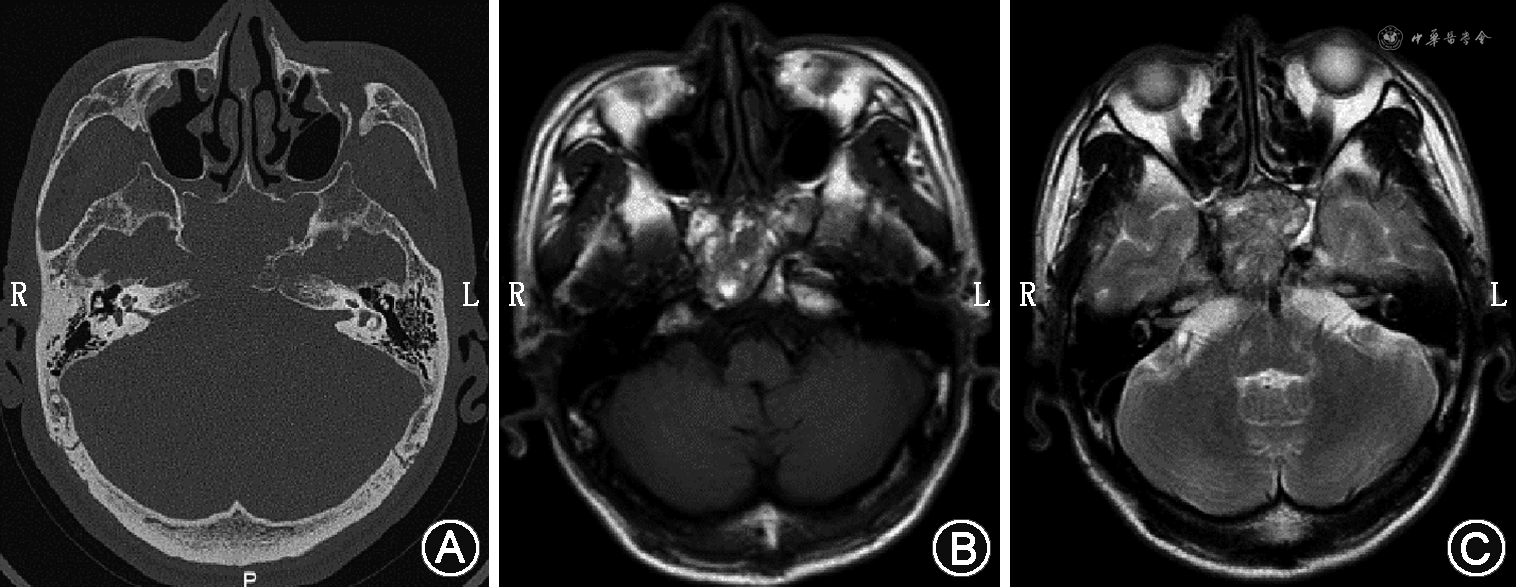

例2 患者男,63岁,因头痛1个月、体检发现“鼻窦肿物”4 d就诊于我院,病程中患者有双侧交替性鼻塞,伴脓涕。患者3年前行左肾摘除术,术后病理回报为玻璃体细胞癌。专科体格检查:鼻内镜下鼻腔内未见明显新生物。鼻窦CT提示左侧筛窦、右侧上颌窦内团块状软组织密度影,边界欠清,密度不均匀,部分突入左侧眼眶内,右侧筛窦、左侧蝶窦及邻近左侧眶内壁、筛骨、蝶窦上壁骨质破坏,右侧上颌窦病灶部分突入右侧筛窦,邻近骨质受压变薄(图3A、B)。MRI示左侧筛窦及右侧上颌窦内不规则等T1稍长T2信号(图3C~F),DWI未见明显高信号,增强扫描不均匀中度强化(图3G、H)。全身麻醉下行手术探查,0°鼻内镜下见左侧中鼻道膨隆,切除钩突,开放上颌窦,切除筛泡基板,开放筛窦,见有暗红色新生物占位,触之易出血,完全切除肿物,颅底骨质完整,左侧眶纸板部分缺如,去除左侧眶纸板见眶内筋膜完整。于右侧下鼻甲前端行泪前隐窝入路,见上颌窦内充满肿物,呈膨胀性生长,界限尚清。切除右侧钩突,开放上颌窦口,完整切除窦内肿物。术后病理回报符合肾透明细胞癌转移。免疫组化染色结果:CK(AE1/AE3)部分弱(+)、CK7(-)、Vimentin(+)、CD10(+)、CAIX(+)、PAX-8(+)、Ki67(阳性率10%)、P504s部分(+)、TFE3(-)。术后随访9个月无复发。